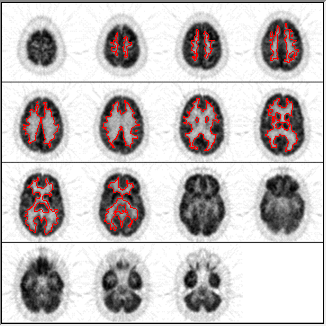

© 1994-2000 Crump Institute for Molecular Imaging

UCLA School of Medicine